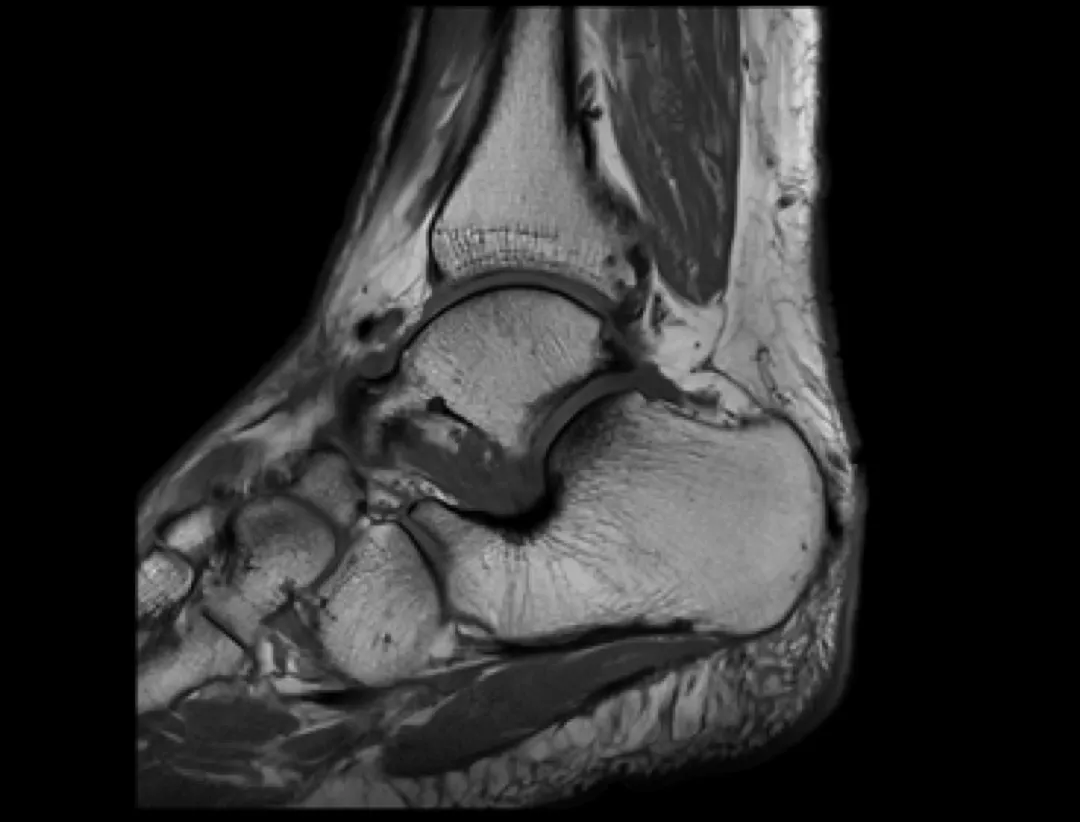

- Rezonans magnetyczny (MRI): To badanie jest znacznie bardziej szczegółowe i pozwala na dokładną ocenę wszystkich struktur stopy kości, chrząstek, więzadeł, ścięgien i mięśni. Jest wykorzystywane w bardziej skomplikowanych przypadkach, gdy istnieje podejrzenie rozległych uszkodzeń lub gdy diagnostyka za pomocą RTG i USG jest niewystarczająca.